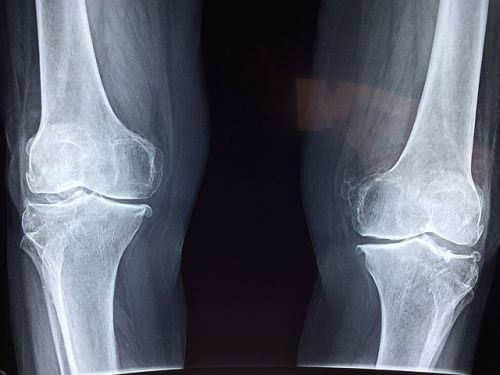

추벽증후군이 있는 경우에는 무릎을 구부린후 펼 때 통증이 발생하는 것으로 유추할 수 있습니다. 또한 무릎이 부어있는 경우에는 MRI촬영을 통해 추벽을 확인할 수 있습니다. 확진의 경우에는 관절경을 통해서 추벽이 두꺼워져 있는 것, 연골이 손상받은 것을 확인합니다.